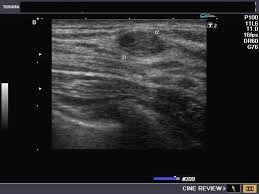

простая киста молочной железы.

На рисунке показано подведение инструмента (тонкая стрелка) к образованию (короткая стрелка) молочной железы.